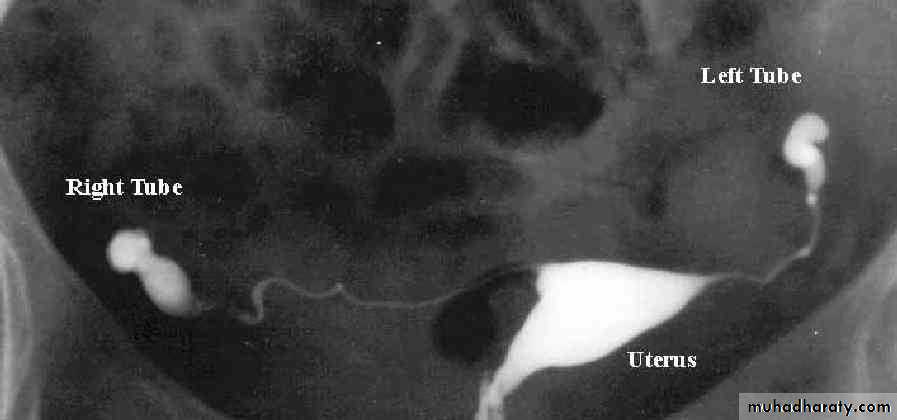

HSG : RT corner is blocked

HSG showing a normal uterus and blocked tubes No "spill" of dye is seen at the ends of the tubes Both tubes are slightly dilated and fluid filled - hydrosalpinxHSG : fibroid is pushing in to the uterus cavity

HSG : bicornuate uterus